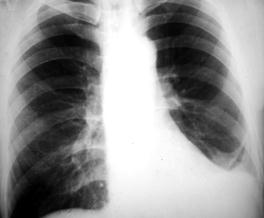

Рис.3. Синдром диссеминации